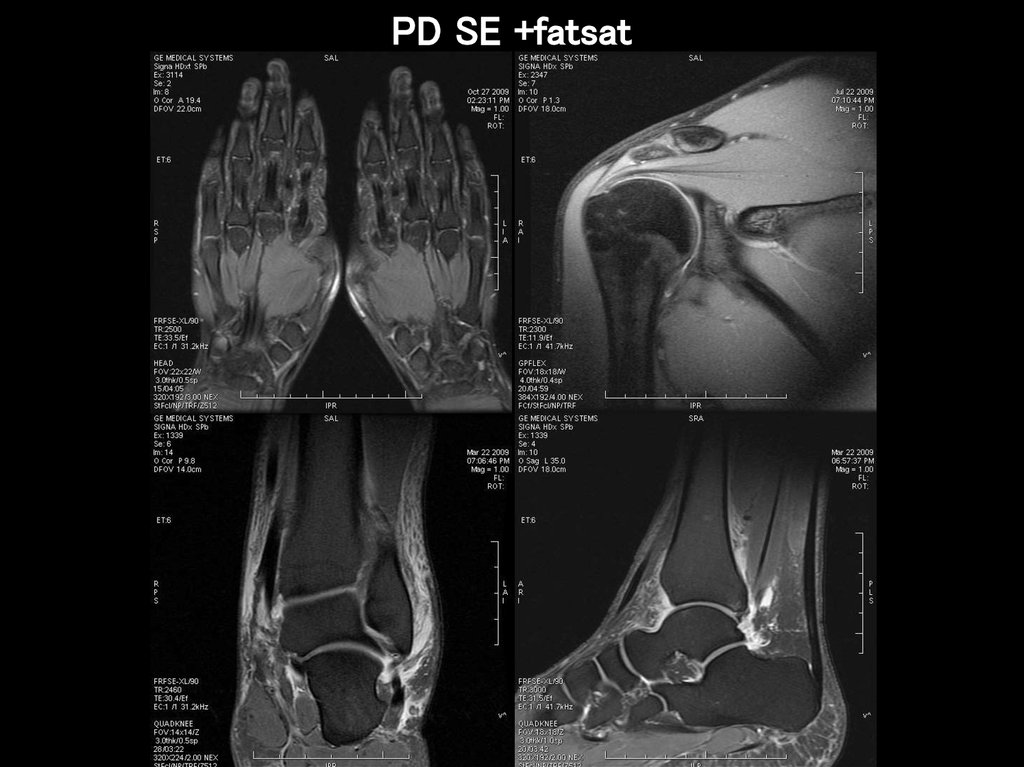

PD SE +fatsat

31.